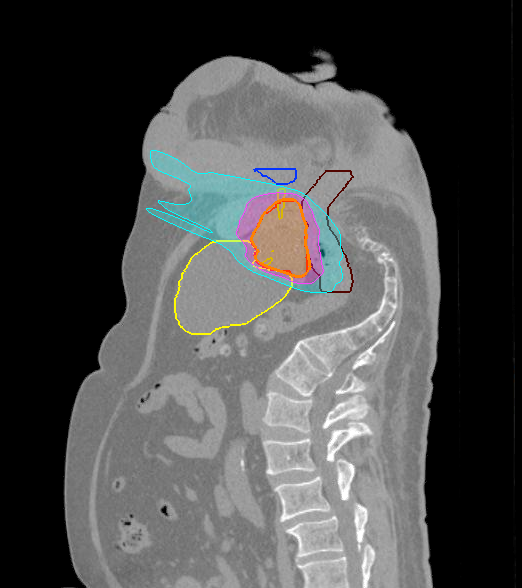

Treatment Plan Images

Dose Distributions

- Prescription to the

84% isodose line - Max. dose 43.15 Gy

New Conformality Index (nCI)

CI = 1.1 / nCi = 1.13

Gradient Index (GI)

GI = 3.34